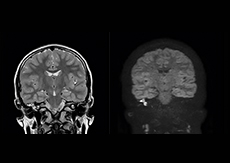

Excellent cholesteatoma imaging with Diffusion TSE

“Imaging cholesteatoma, benign tumors of the middle ear, has been a huge challenge,” says Dr. Heggelman. “We used to do CT, but then we were unsure if we were looking at an inflammation or a cholesteatoma. Also determining if residual cholesteatoma exist after surgery or visualizing recurrence used to be very difficult. Adding Diffusion TSE in our MRI protocol now effectively addresses this.”

“Diffusion TSE is far less sensitive to susceptibility differences than previously used EPI sequences. We appreciate the high resolution and the robustness of the sequence. The quality is so good that our confidence has increased. Also our ENT (ear, nose, throat) physicians are excited about the high resolution, the excellent lesion delineation and the sensitivity and specificity.”